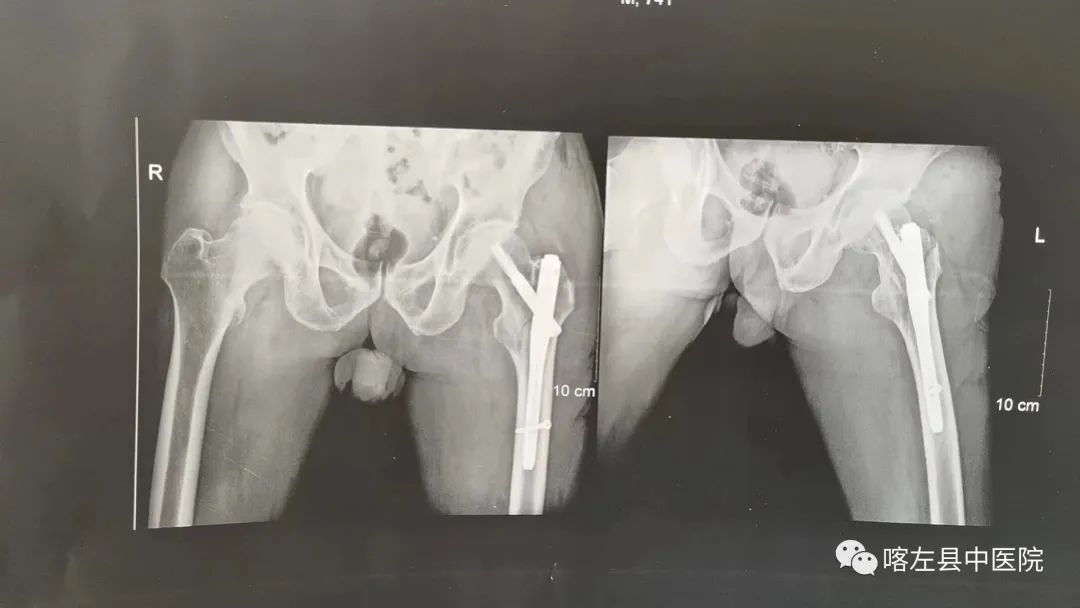

由于该患者患有急性脑梗死基础病,保守治疗将面临治愈率低、长期卧床病并发症多发、远期疗效差等问题,会严重损害该患者的健康、影响其生活质量。为了最大程度的保证该患者的生命健康和生活质量,解决患者和家属的心头难事,县中医院副院长、骨伤科主任杨永清带领骨科团队对患者的病情、既往病史和检查结果进行了全面细致的评估,最终决定为该患者实施“c型臂透视下闭合复位PFAN内固定术”。手术过程顺利,手术时间大约25分钟,术中出血仅80ml。

手术次日,该患者就可以拄拐下床站立,短距离行走。术后2周切口拆线,目前该患者已回家并生活自理。